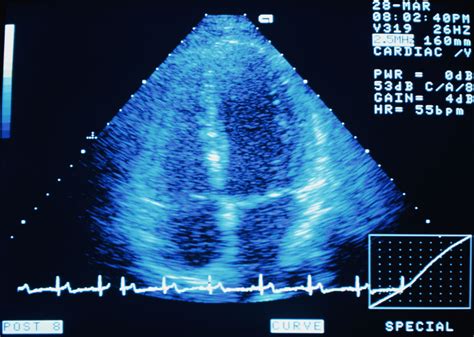

The Bubble Test Heart, also known as the Bubble Contrast Echocardiography, is a non-invasive diagnostic procedure used to detect abnormalities in the heart's structure and function. This test involves injecting a small amount of saline solution into a vein, which is then agitated to create microbubbles. These bubbles are visible on an echocardiogram, allowing cardiologists to observe the flow of blood through the heart and identify any potential issues.

• Imaging: An echocardiogram is performed, which uses ultrasound waves to create images of the heart. The microbubbles enhance the contrast, making it easier to see the blood flow.

• Analysis: The cardiologist analyzes the images to detect any abnormalities, such as shunts, valve regurgitation, or other structural issues.